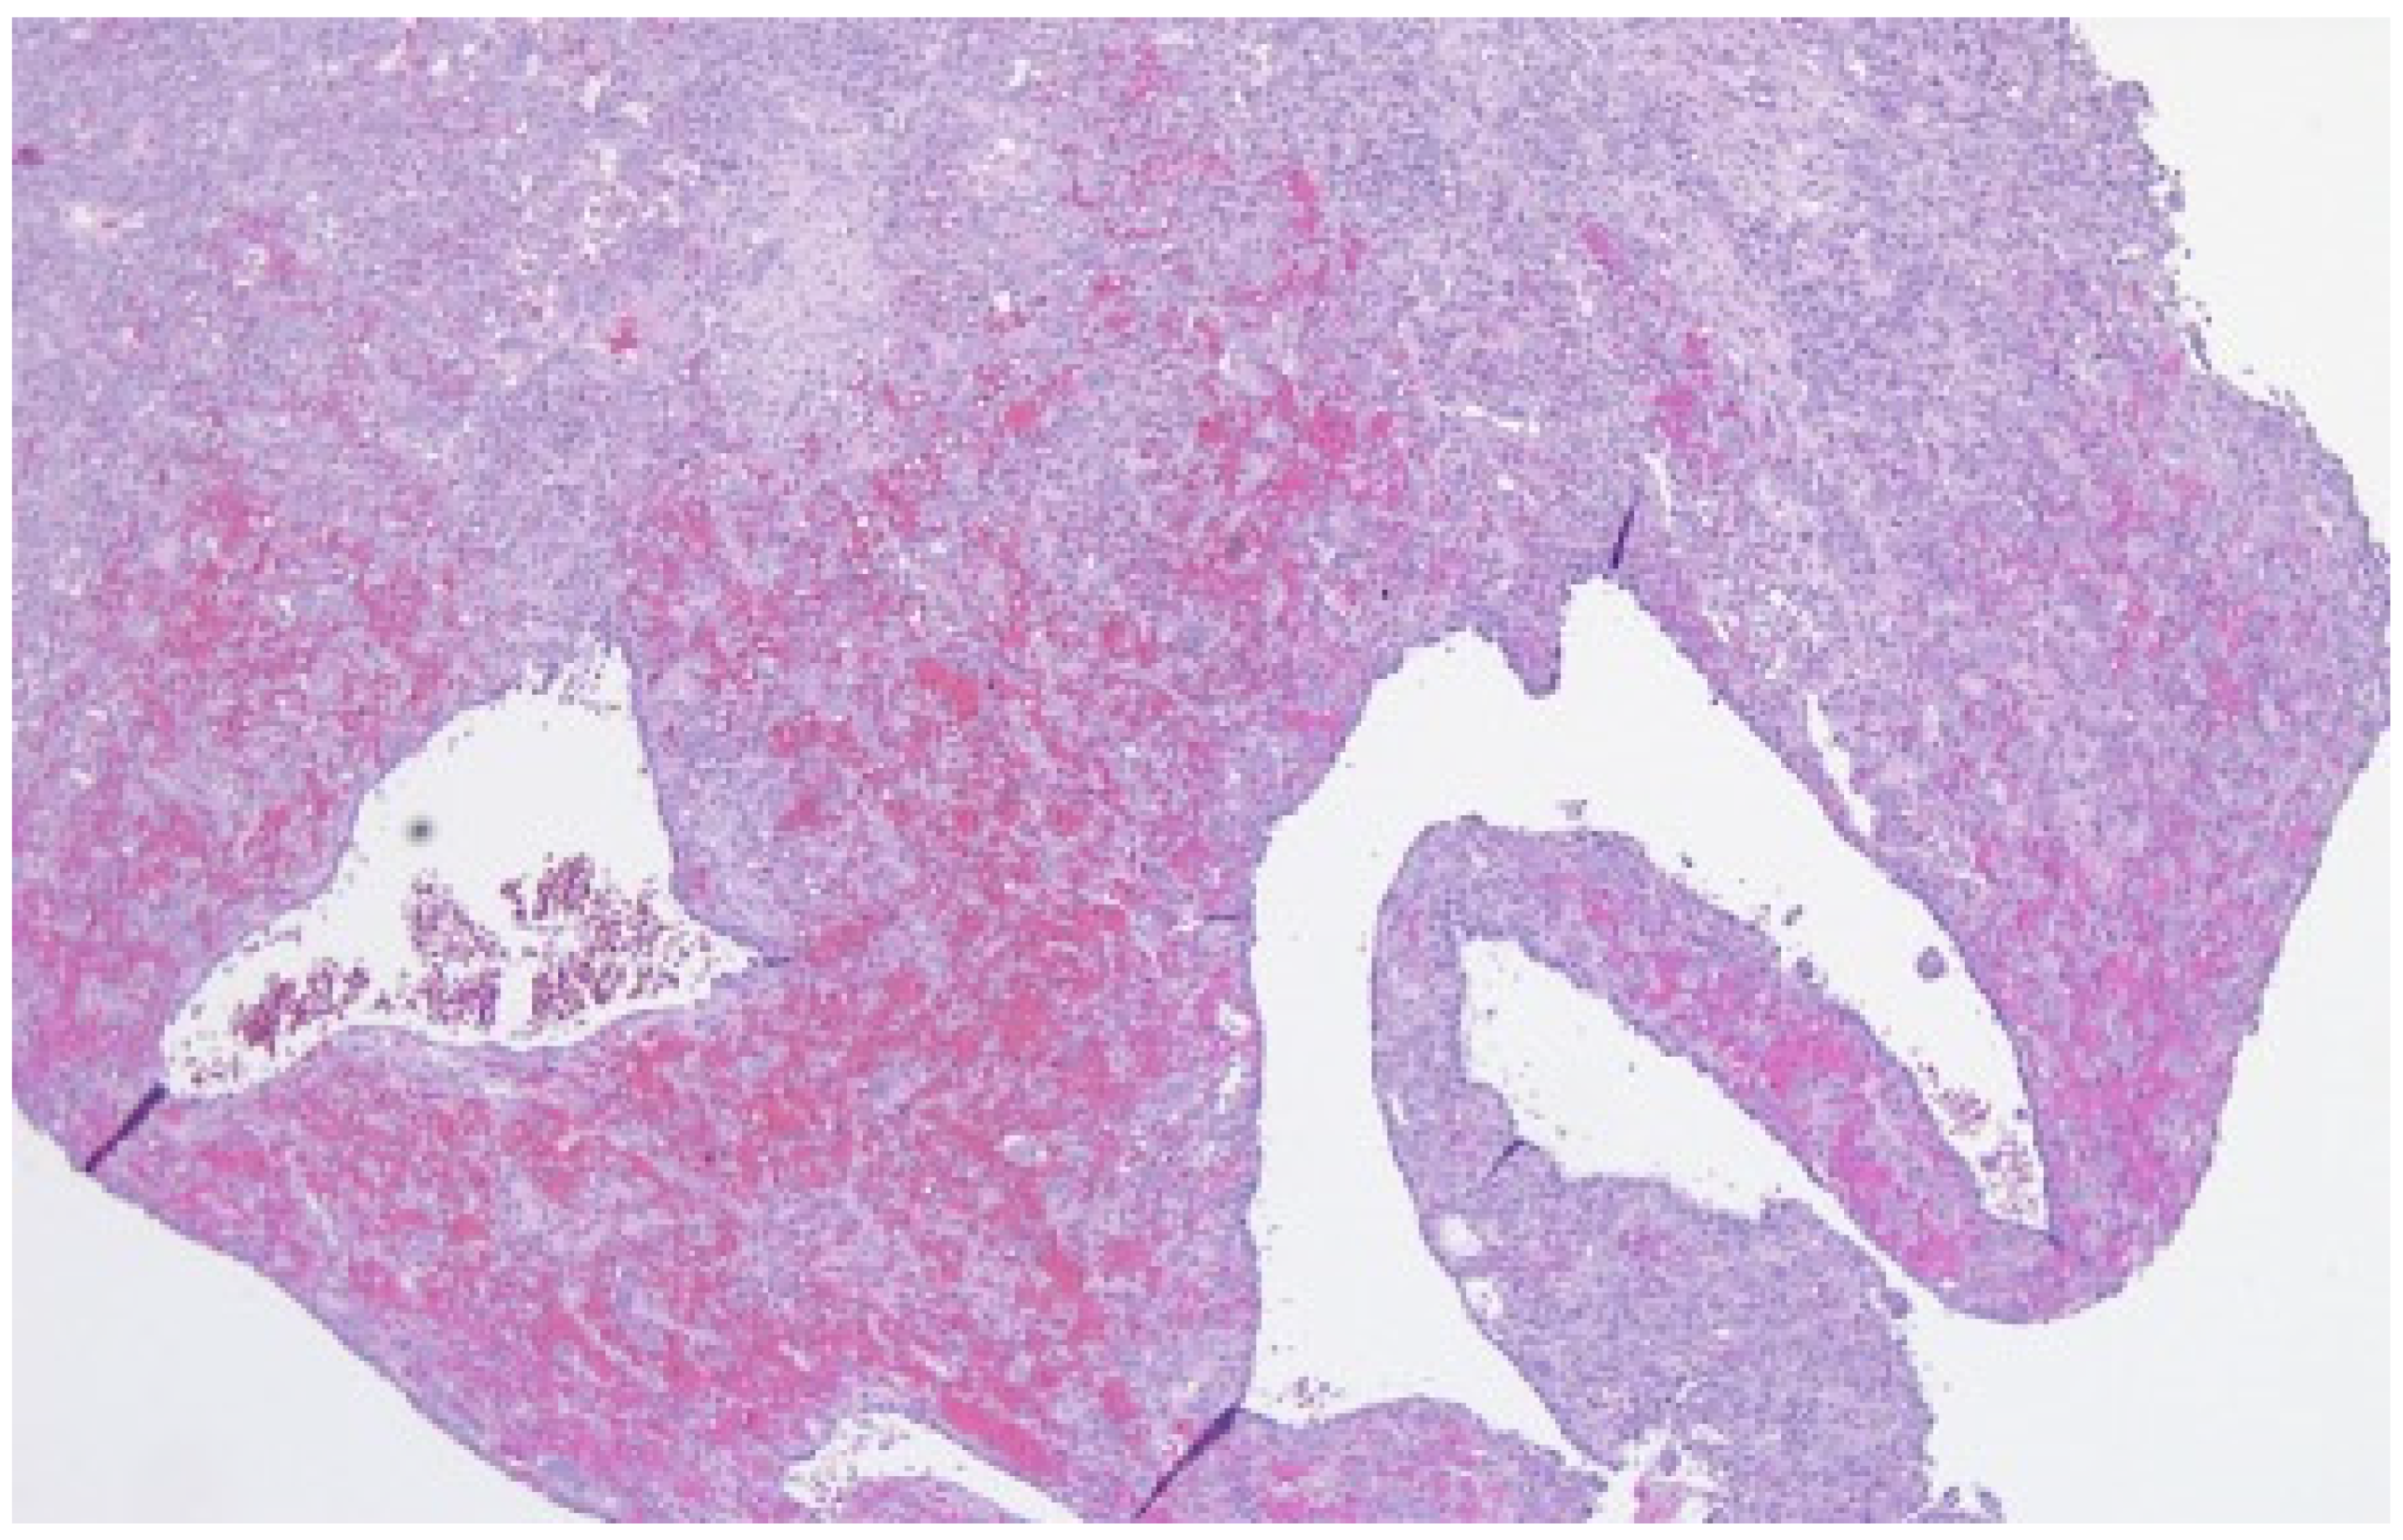

- Docquier, P.L.; Delloye, C.; Galant, C. Histology can be predictive of the clinical course of a primary aneurysmal bone cyst. Arch. Orthop. Trauma Surg. 2010, 130, 481–487. [Google Scholar] [CrossRef]